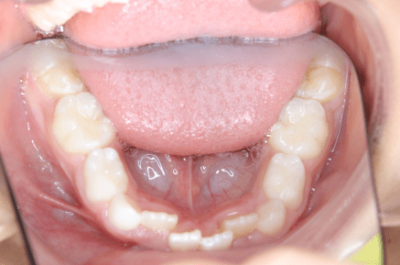

3.叢生(そうせい)、でこぼこ

叢生とは、歯並びがデコボコの状態のことを指します。

歯並び・かみ合わせが悪い状態を不正咬合といいます。

その不正咬合の原因はひとつではありません。